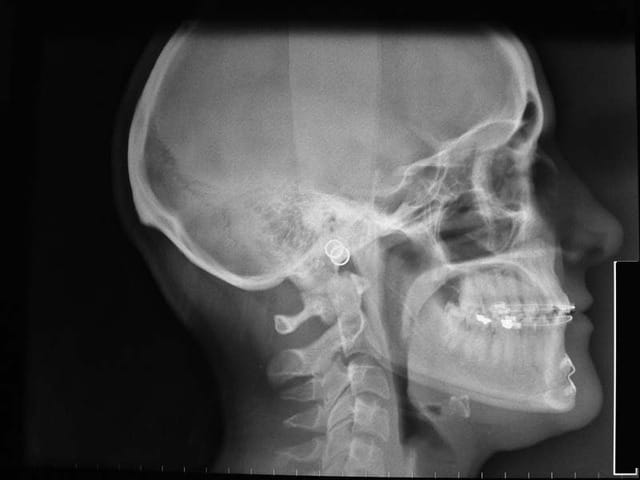

je la traite par les techniques de friction faible, et voici le résultat 1 an après

je ne suis pas en inversé d’articulé Ant. comme je pensais me retrouver !!!

et son profil s’est bien modifié

On voit bien le changement de profil sur les radios .

la génioplastie n’a pas été une réussite la 1° fois, toutes les Rx. sont avec le résultat de cette génioplastie

pour ceux qui ne se rappellent pas bien de l’analyse esthétique de Ricketts, voici qq. tracés